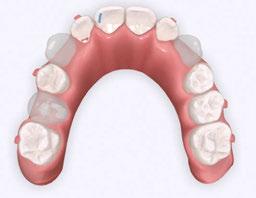

Unlike other Phase 1 appliances I’ve used, Angel Aligner KiD was built for adaptability. It incorporates unique features like curved turbos, eruption guides, and specialized trimlines that help guide developing dentition while respecting the nuances of a child’s oral environment. Additionally, features such as A6 mandibular advancement, angelButton™, and the angelHook™ Maxillary Protraction Solution with Facemask compatibility open new possibilities for skeletal correction in a comfortable, removable format. Angel Aligner KiD’s capacity to support myofunctional correction, manage eruption, and guide skeletal

The primary objectives were to expand both the upper and lower arches, consolidate anterior space, and apply a mesial root tip to the U2s to protect them from the U3 trajectory. My additional goals included aligning the arches and guiding the canines without using fixed appliances, all while respecting my patient’s comfort and cooperation threshold.

For expansion, I used my typical aligner expansion protocol of expanding the U6s first, followed by the Uc,d,e’s. For the lower, I requested uprighting of the lower posterior to coordi-

nate with the upper arch (leveling of the Curve of Wilson). I also wanted to apply mesial root tip of the U2s to place them in a more protected position, away from the ectopic U3s. I selected Angel Aligner KiD because of its comfort, removability, and ease of hygiene for a sensory-sensitive patient.